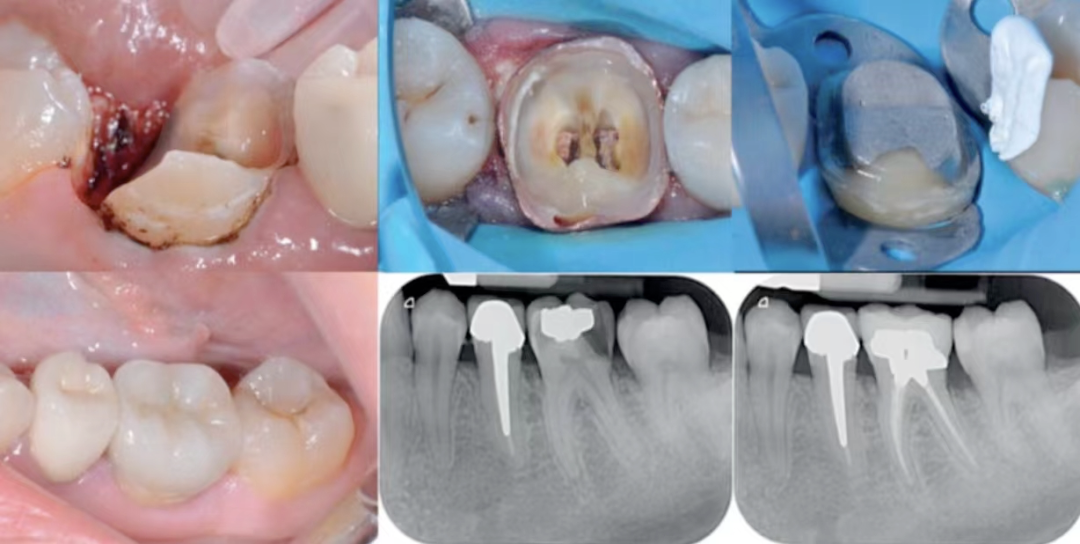

图1:龈下较深,游离龈缘下4mm,采用电刀进行DMA。封闭是通过特氟龙实现的。非解剖(无基质)银汞合金重建内部,进行无肩台预备,用来消除自由手DME带来的悬突,并产生箍效应。

图2:龈下很深,采用电切的方法进行边缘采集。封闭是使用特氟龙。非解剖(无基质)银汞合金内部重建,进行了E-max全覆盖。

图3:远中龈下边缘。通过电切获得深部边缘。橡皮障实现隔离,解剖DME是通过楔子和成型片,特氟龙辅助实现的。粘接E-max嵌体。

图4:非解剖性DME和无肩台预备。龈下边缘在颊侧和远中。通过电切进行DMA。用橡皮障和特氟龙进行隔离。徒手进行DME。为了消除DME带来的悬突,获得箍效应,进行了无肩台预备。

图9:DME和牙周原理。术前术后临床影像。以检查边缘骨水平。通过DME和氧化锆(垂直型预备)取代龋坏组织。

图10:通过橡皮障和特氟龙实现隔离。非解剖DME,通过可流动的复合材料实现,徒手放置。根管治疗保留后才进行垂直预备,氧化锆单冠修复。

图11:锯齿状波浪边缘和极端凹陷边缘,这种情况是用任何成型系统都无法完美控制的。

图12: DME和邻面几何轮廓。术前术后X线,临床医生无法复制自然的邻面解剖轮廓到DME上,牙科技师也无法创建邻面解剖轮廓。